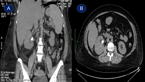

Pancreas graft salvage after successful endovascular treatment of Y graft pseudoaneurysm

V A L Huurman and J H P Lardenoye

Journal of Surgical Case Reports, Volume 2019, Issue 5, May 2019, rjz124, https://doi.org/10.1093/jscr/rjz124